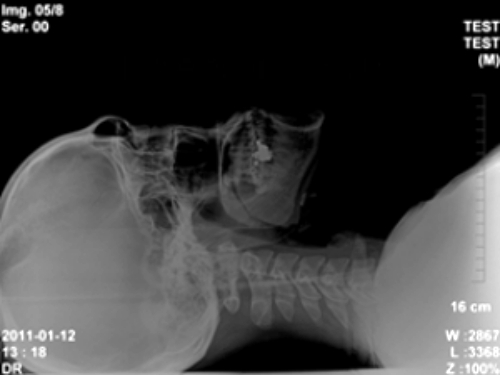

머리와 목 자세(head & neck posture)에 좋은 편한 베개(comfortable pillow)의 조건은, 우리가 바로 누웠을 때(supine) 변곡점(inflection point)들을 지지(supporting)할 수 있는 베개(pillow)입니다. 그러니까 후두골(occipital bone)과 목뼈(cervical) 1번, 목뼈(cervical) 7번과 등뼈(thoracic) 1번입니다. 해당 영역(area)들은 서로 다른 성격이 뚜렷하게 내재된 골격(skeleton)들의 경계선(boundary line)입니다. 이 지점(area)에서의 부정한 골격(skeleton)의 위치(position)와 자세(posture)는 서로 다른 뼈(bone)들에 대해 잘못된 위치(faulty position)로 전이된 상태(transferred condition)에서 수면(sleep)을 취하게 될 수 있습니다.

경추(cervical)는 기본적으로 전방(anterior)으로 경사진 만곡(inclined curve)의 형태(shape)를 지닙니다. 이때 가장 많은 만곡도(curved degree)는 보편적으로 목(neck)의 중간 영역(center area), 혹은 중간(center)에서 약간 하부 영역(inferior area)에 치우쳐져 있습니다. 그러니까 이러한 영역(area)을 떠받칠 수 있는 베개(pillow)가 좋습니다.

다만 중요한 것은 사람마다 척추 자세(spinal posture)와 목 상태(neck condition) 등에 따라, 현재 형성되어있는 목(neck의 만곡도(curved degree)가 다른 만큼, 개인차를 고려하여 만곡도(curved degree)에 적절히 충족될 수 있는 만큼의 지지도(supporting degree)가 필요합니다. 그러니까 예를 들어 과전만 형태(hyperlordosis shape)의 사람이라면 그만큼 전방(anterior)으로 치우진 만곡도(curved degree)가 증가되어있으니, 해당 영역(area)을 더 크게 보충(supplement)시키기 위해 목(neck)의 중하단 영역(middle & inferior area)을 지면(ground)으로부터 채워줄 수 있는 베개(pillow)가 필요할 것입니다. 반면, 정상 만곡(normal curve)에서 반대로 벗어난 일자목(straight neck)의 형태(shape)나 역C자 형태(inverse C shape)의 목(neck)은 오히려 우리에게 하여금 경추베개(cervical pillow)라고 하는 것들이 현재 상태(condition)에서는 좋지 않을 수 있습니다. 이런 대상자들은 오히려 바로 누운 자세(supine posture)에서도 정상적인 만곡도(curved degree)로 어느 정도조차 회복(recovery)되는 형태(shape)로 자세(posture)가 잡혀 지지 않는다면, 지면(ground)과의 거리(distance)만큼만 보충(supplement)될 수 있도록 목(neck)을 받쳐주면 됩니다. 일부러 처음부터 정상 만곡도(normal curved degree)를 만들 수 있는 베개(pillow)를 선택(choice)하는 것이 아닌, 비교적 비정상적인 베개(abnormal pillow)의 선택(choice)으로 보일지라도 해당 대상자에게는 일자목(straight neck)이나 역C자 형태(inverse C shape)를 존중하는 베개(pillow)가 실제 대상자에게는 더욱 편한 베개(comfortable pillow)가 됩니다.